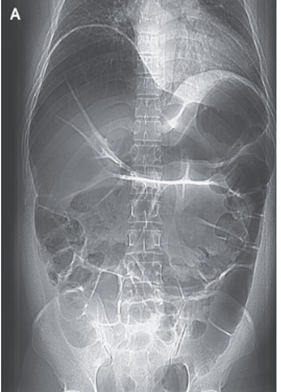

腹部X-pでは大腸の拡張が目立ち、小腸のループ形成も認めた。

CT検査・注腸バリウム検査が施行され、脾臓屈曲部に高度の閉塞があることが判明した。